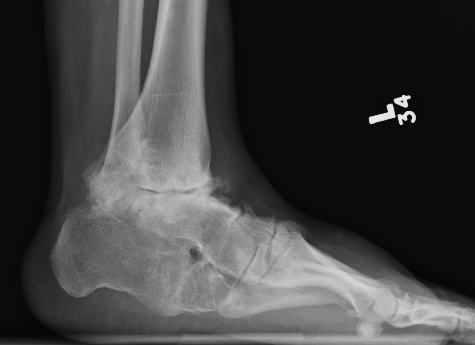

Combined ankle and subtalar joint osteoarthritis

Talar AVN

Trauma

Severe Deformity - acquired flat foot / neurological conditions / Charcot /

Ankle fracture in elderly patient with poor skin and co-morbities

Rheumatoid arthritis

Severe acquired planovalgus

Fragility fractures